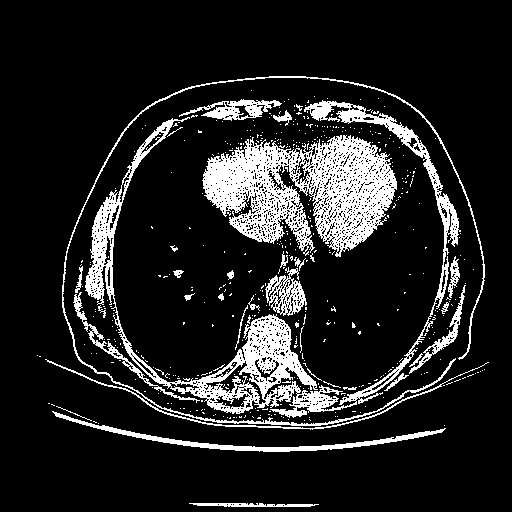

Slice 70 Targeting Evaluation

Patient ID: BC23122020

Model: cytran

Slice: Slice_70

Slice Thickness: 2.5mm

Conversion: NATIVE β VENOUS

4Γ3 grid: Rows show different image types (Original NATIVE, Reconstructed NATIVE, Original VENOUS, Generated VENOUS), Columns show windowing techniques (No Window, Lung Window, Mediastinum Window)